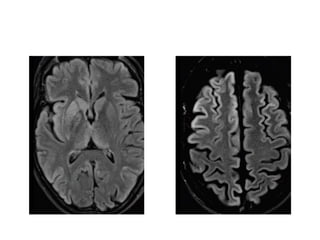

• The exudates are isointense

to CSF in T2WI but do not

supress in FLAIR.

• D/D for hyperintensity in

the Subarachnoid cistern

and sulci on FLAIR /

leptomeningeal

enhancement : SAH;

Meningitis; CSF metastasis ;

Oxygen or protocol therapy